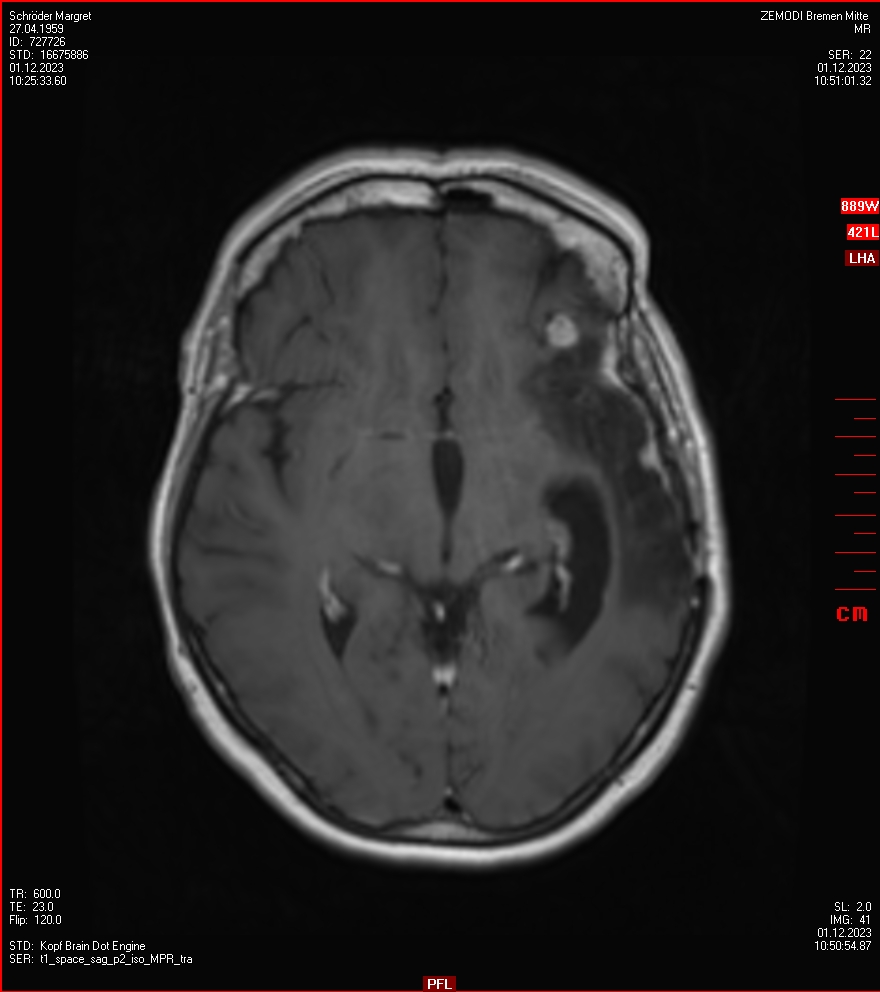

Die letzten drei Bilder Zeigen aus meiner Sicht den Tumor, der im Jahr 2021 bestrahlt wurde.

Zum Vergleich nun auch die Bilder vom 1.12.2023:

Ich denke, in den letzen 12 Monaten sind da ein paar Rezidive gewachsen,  vor 12 Monaten waren sie auch schon zu erkennen - vorher noch nicht. Nun hoffe ich auf den Rat des Spezialisten. Hoffendlich kann man etwas machen.